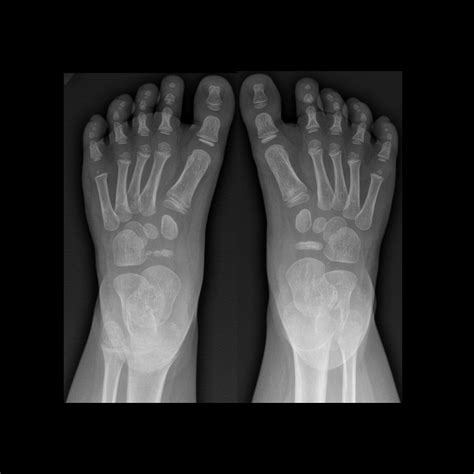

Pediatric Radiology is a subspecialty of radiology focused on the imaging of infants, children, and adolescents. Because children are not simply "miniature adults," their bodies undergo constant growth and development. Bones are still ossifying, organ systems are maturing, and metabolic rates are significantly higher than those of adults. These factors necessitate highly specific protocols for diagnostic imaging.

The field covers a wide array of imaging modalities, each chosen specifically for the diagnostic question at hand. Radiologists in this field undergo extensive training to distinguish between normal developmental variations and genuine pathology. This expertise is crucial for parents and primary care physicians alike, as it ensures that the diagnostic process is as accurate and minimally invasive as possible.

• X-rays: Often the first line of defense for bone fractures or lung issues.

X-ray Minimal Bone fractures, pneumonia, chest congestion